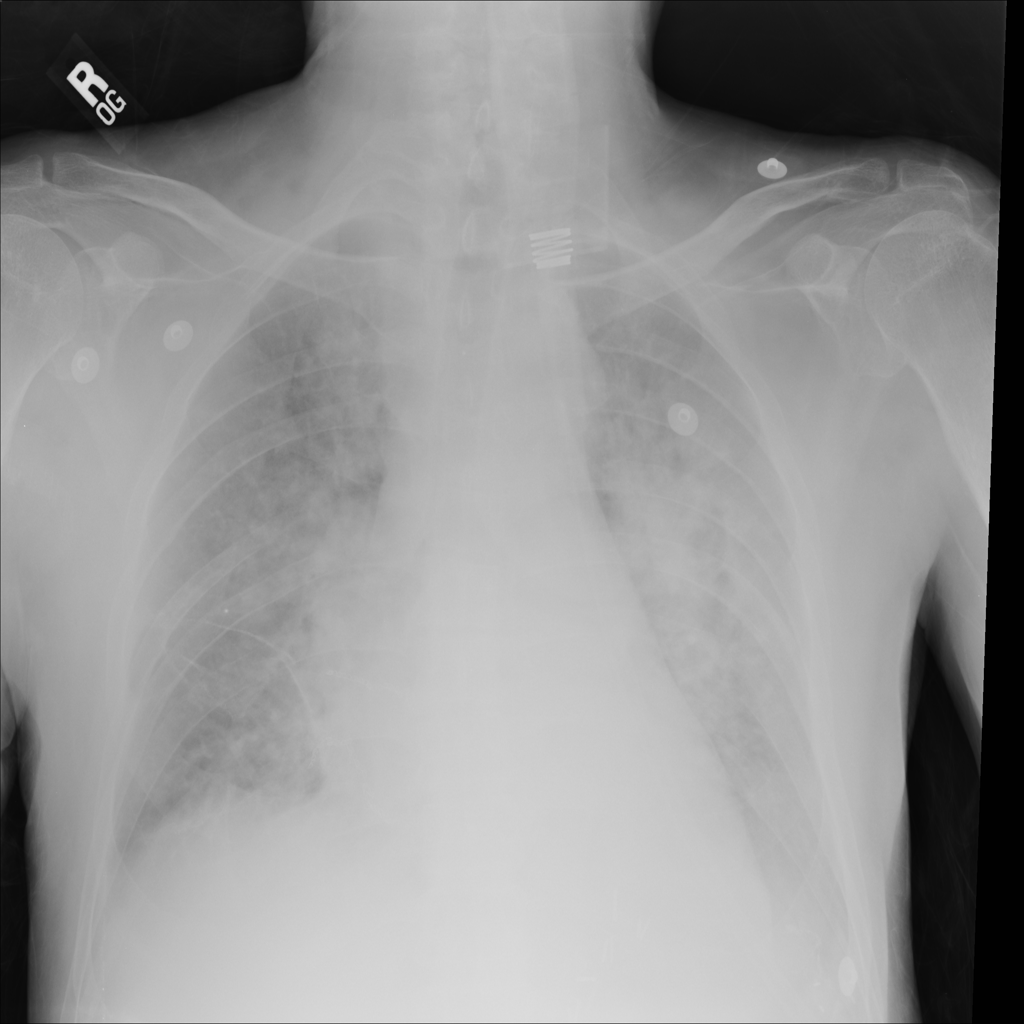

PAT-EBE1 · IMG-019Pneumonia

PAT-EBE1 · IMG-019

AP